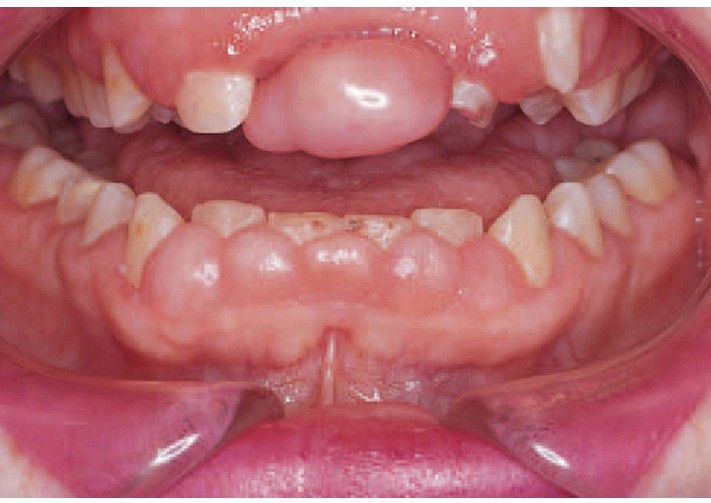

Gingival hyperplasia due to phenytoin. Characteristically the fi brous overgrowth has originated in the interdental papillae, which become bulbous but remain fi rm and pale. Localised gross enlargement such as that around the upper central incisor may result and can form a plaque trap.